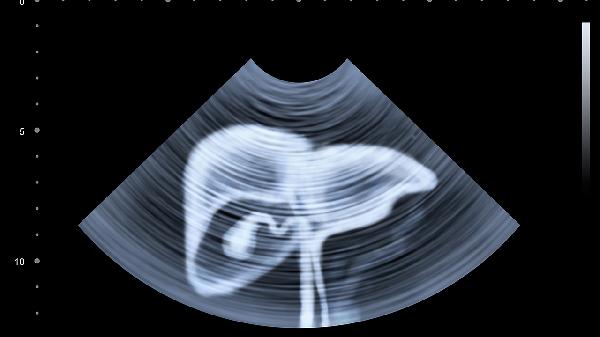

急性胃穿孔是什么原因引起的

急性胃穿孔主要由胃潰瘍、外傷或胃部腫瘤導致,需立即就醫處理。常見(jiàn)誘因包括長(cháng)期胃潰瘍未愈、腹部外力撞擊、胃癌侵蝕胃壁等,治療需結合藥物、手術(shù)及生活方式調整。